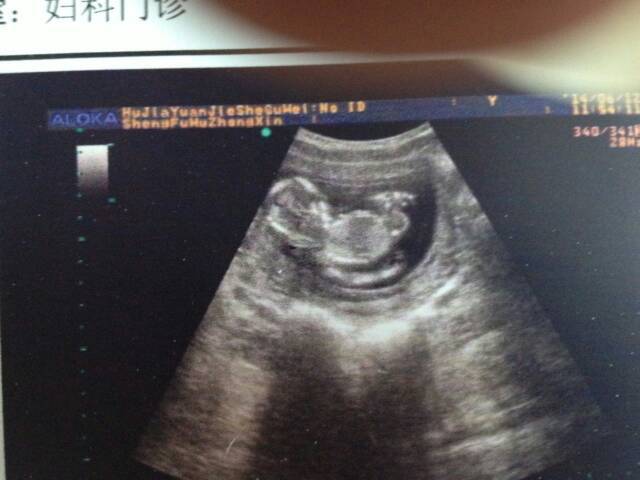

您说的这种治疗方法是矫正胎位不正的。对于脐绕颈效果不大。 脐绕颈在临床上很常见,不一定都需要剖腹产,只有胎头不下降或胎心有明显异常(胎儿窘迫)时,才考虑是否需要手术。平时要注意的就是减少震动,保持睡眠左侧位,注意胎动,定期做好产前检查。

你好 请不要担心 宝宝现在的发育状况良好 现在见胎儿二有脐绕颈 建议隔期进行孕期检查 及时了解胎儿的发育的情况 祝你好孕